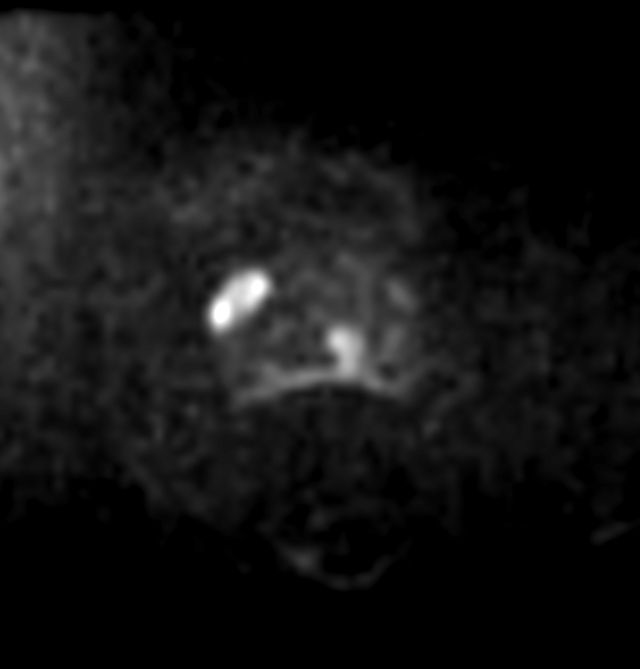

Diffusion - b800

-

Diffusion - b2000